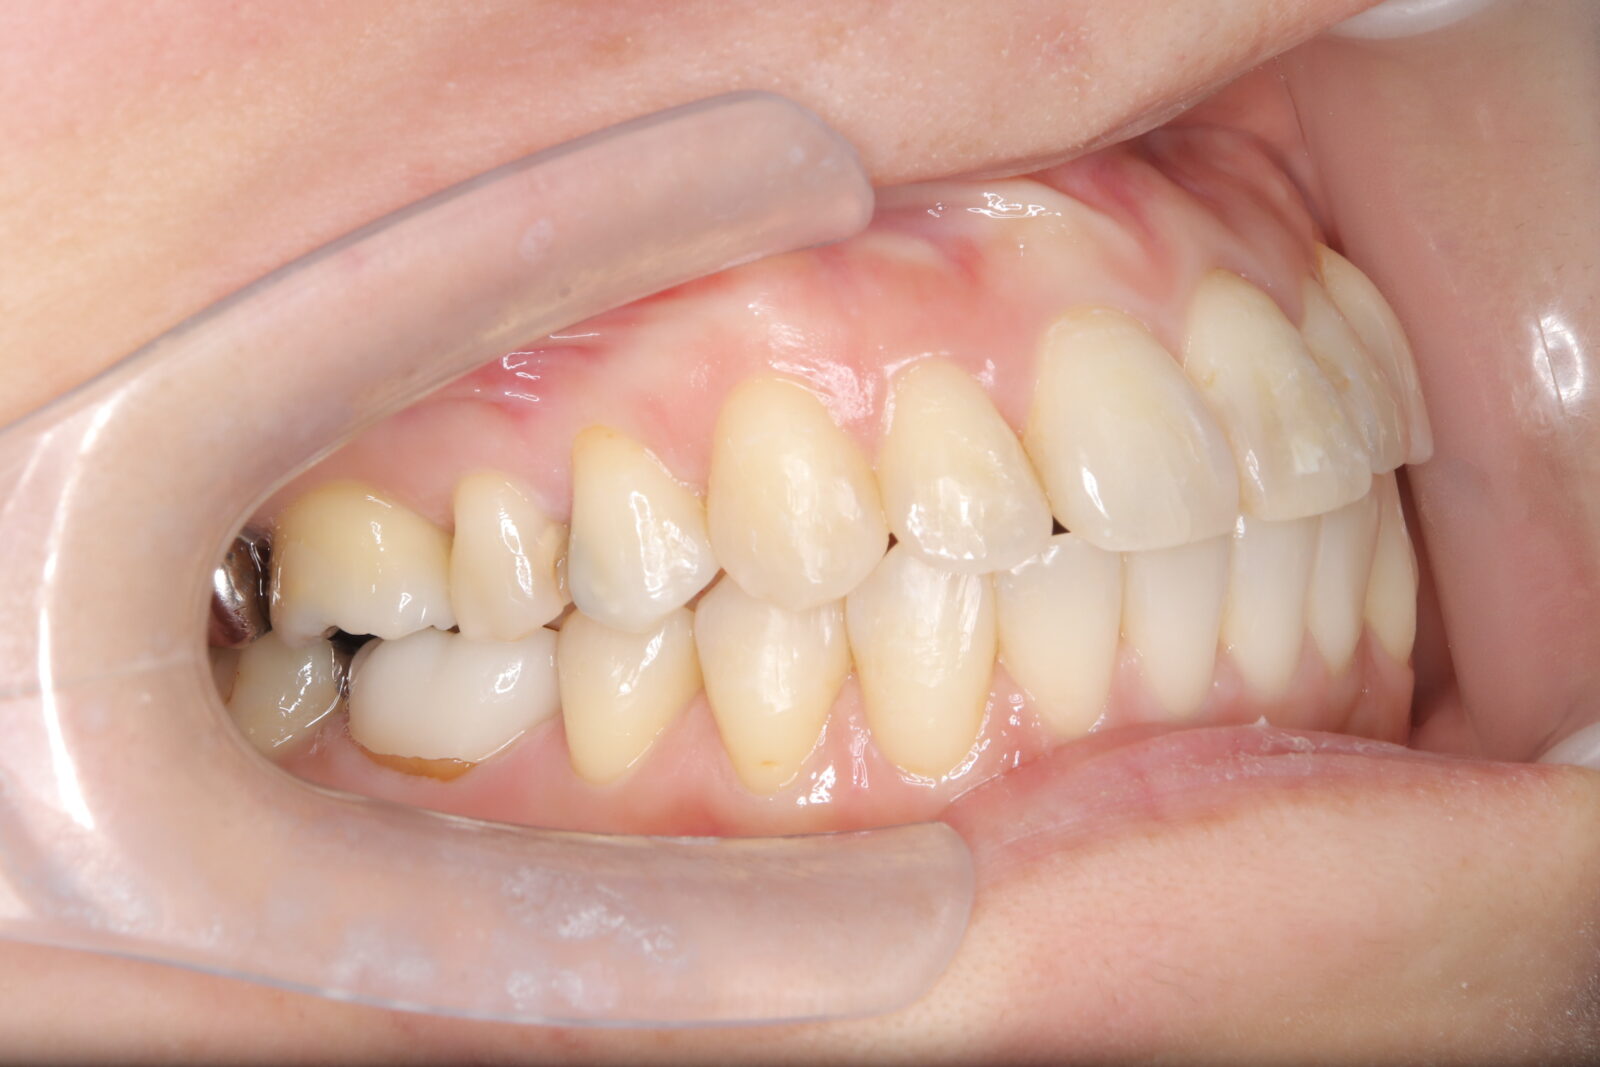

インビザライン(全体矯正)+ホワイトニングコース+セラミック治療の症例

過去にワイヤー矯正で治せなかったクロスバイト。インビザライン(全体矯正)とホワイトニングとセラミック治療で綺麗な笑顔へ。

・費用:726,000円(税込) ※ホームホワイトニングと右上6番ジルコニアクラウン含む

・治療期間:15ヶ月

・通院回数:10回

・32歳女性

-リスクと副作用-

・長時間マウスピースを装着するため、むし歯や歯周病のリスクがある。治療後はリテーナーを装着しないと後戻りしてしまうリスクがある。

・ホワイトニング剤の影響で知覚過敏が起こる可能性がある。色が徐々に戻る可能性がる。

・セラミック:過度な衝撃によって割れることがある。